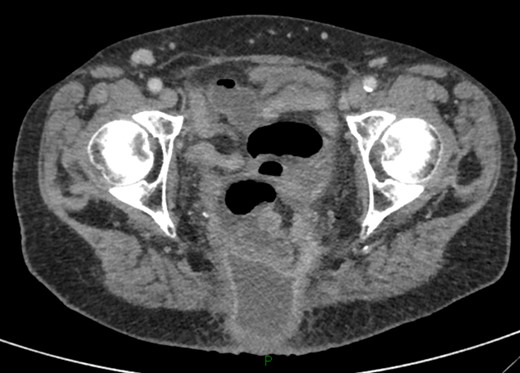

On examination, she was febrile. Her abdomen was generally tender. Bowel sounds were present and up to that time her stoma was working. Her perineal hernia was red and tender. Her initial CXR (Fig. 1) did reveal a sliver of gas underneath her right hemidiaphragm and in keeping with her abdominal findings she progressed to further imaging. CT abdomen pelvis with contrast showed pneumoperitoneum (Fig. 2) with ‘a tiny pocket of air is also seen adjacent to a loop of bowel in the pelvis posterior to the bladder’. ‘Exact site of perforation has not been demonstrated but could possibly be in the bowel loops in the perineum’ (Figs 3 and 4).

CT showing small bowel loops in pelvis with perineal hernia and free fluid.